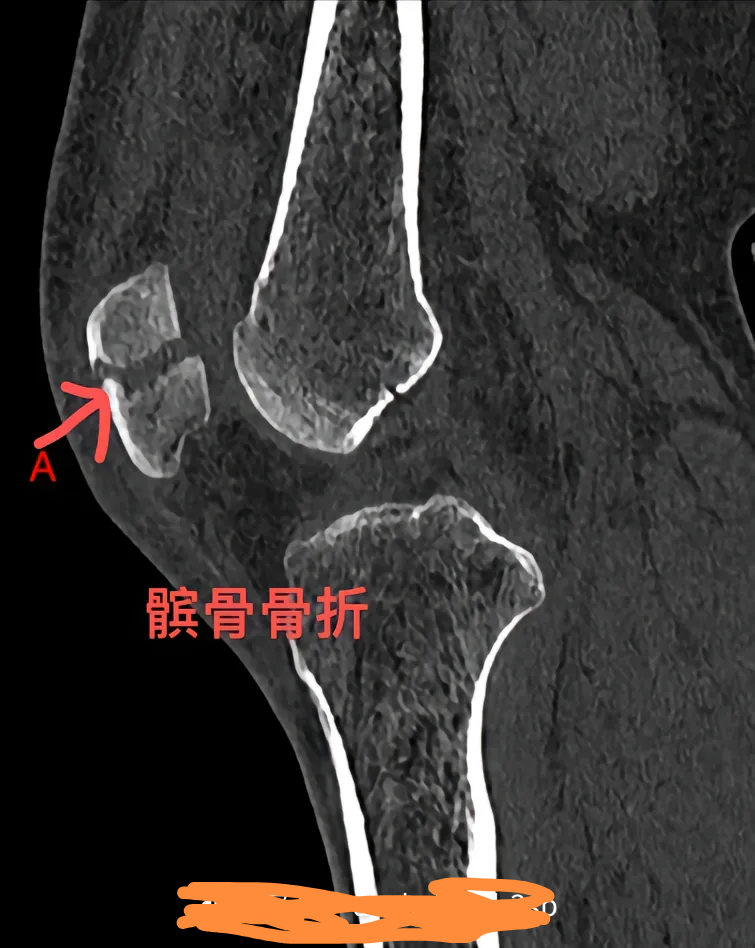

骨折后如何处理